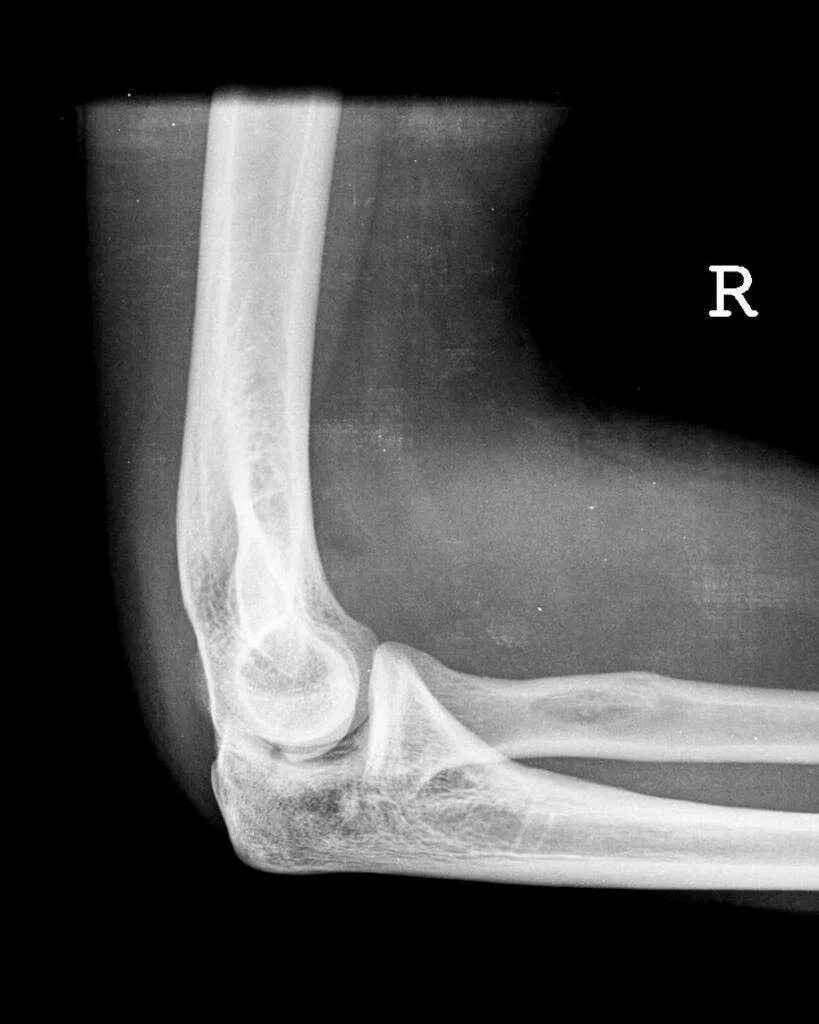

Подвывих локтевого сустава у ребенка